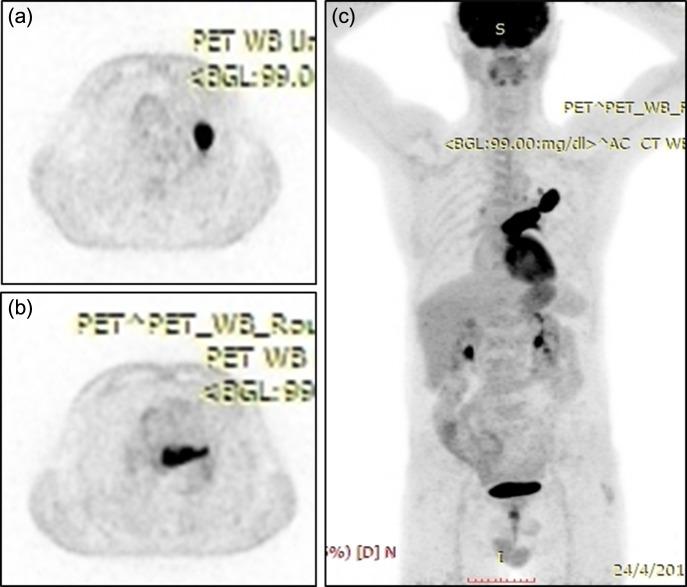

A 61-year-old man presented with dyspnea, left thoracic pain and productive cough. Chest computed tomography demonstrated a solid mass of the left upper lobe, 2.9 × 1.8 cm in size, which had irregular borders and appeared to infiltrate and totally occlude the upper left pulmonary vein extending up to the left atrium (LA) with thrombus formation. The patient underwent median sternotomy and left pneumonectomy, combined with LA thrombus resection under cardiopulmonary bypass (CPB) with bicaval cannulation. The LA was partially resected and the intracavitary thrombus was completely removed. The surgical margins were free of tumor cells. Episodes of embolism were not observed during surgery. The patient was successfully weaned from CPB. The postoperative course was uncomplicated. Pathological examination of the resected specimen revealed giant cell carcinoma.

一名61岁男性患者出现呼吸困难、左胸痛和咳痰。胸部计算机断层扫描显示左肺上叶有一个实性肿块,大小为2.9×1.8厘米,边界不规则,似乎浸润并完全阻塞了左上肺静脉,血栓形成一直延伸至左心房(LA)。患者接受了正中胸骨切开术和左肺切除术,并在体外循环(CPB)双腔插管下联合进行左心房血栓切除术。左心房部分切除,腔内血栓完全清除。手术切缘无肿瘤细胞。手术期间未观察到栓塞事件。患者成功脱离体外循环。术后过程无并发症。切除标本的病理检查显示为巨细胞癌。